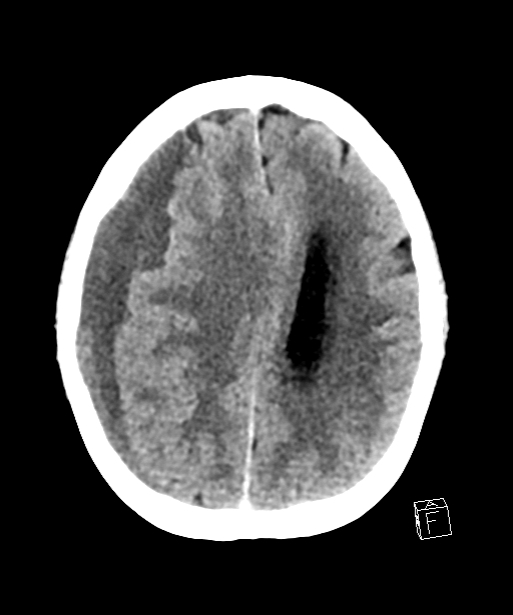

CT Scan print Pre treatment - subdural hematoma

Pre treatment CT head: subdural hematoma